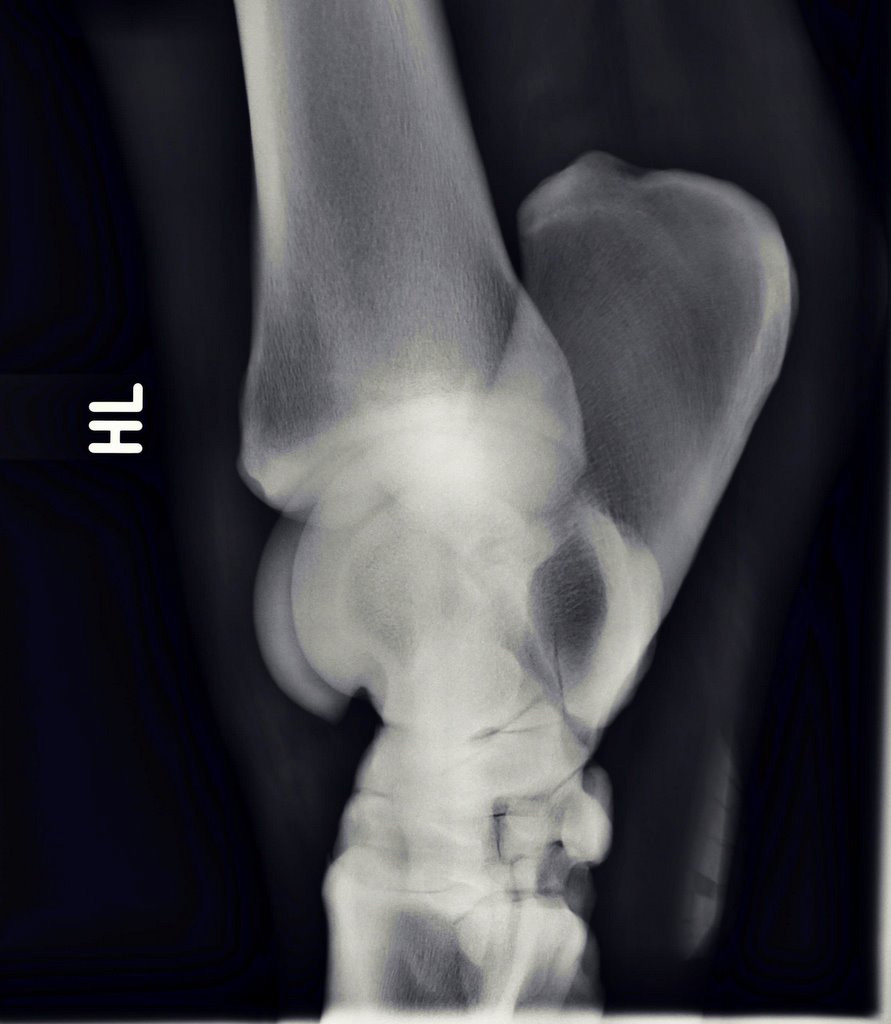

Illustrative Mindeststandardaufnahmen zur Beurteilung nach dem Röntgenleitfaden: